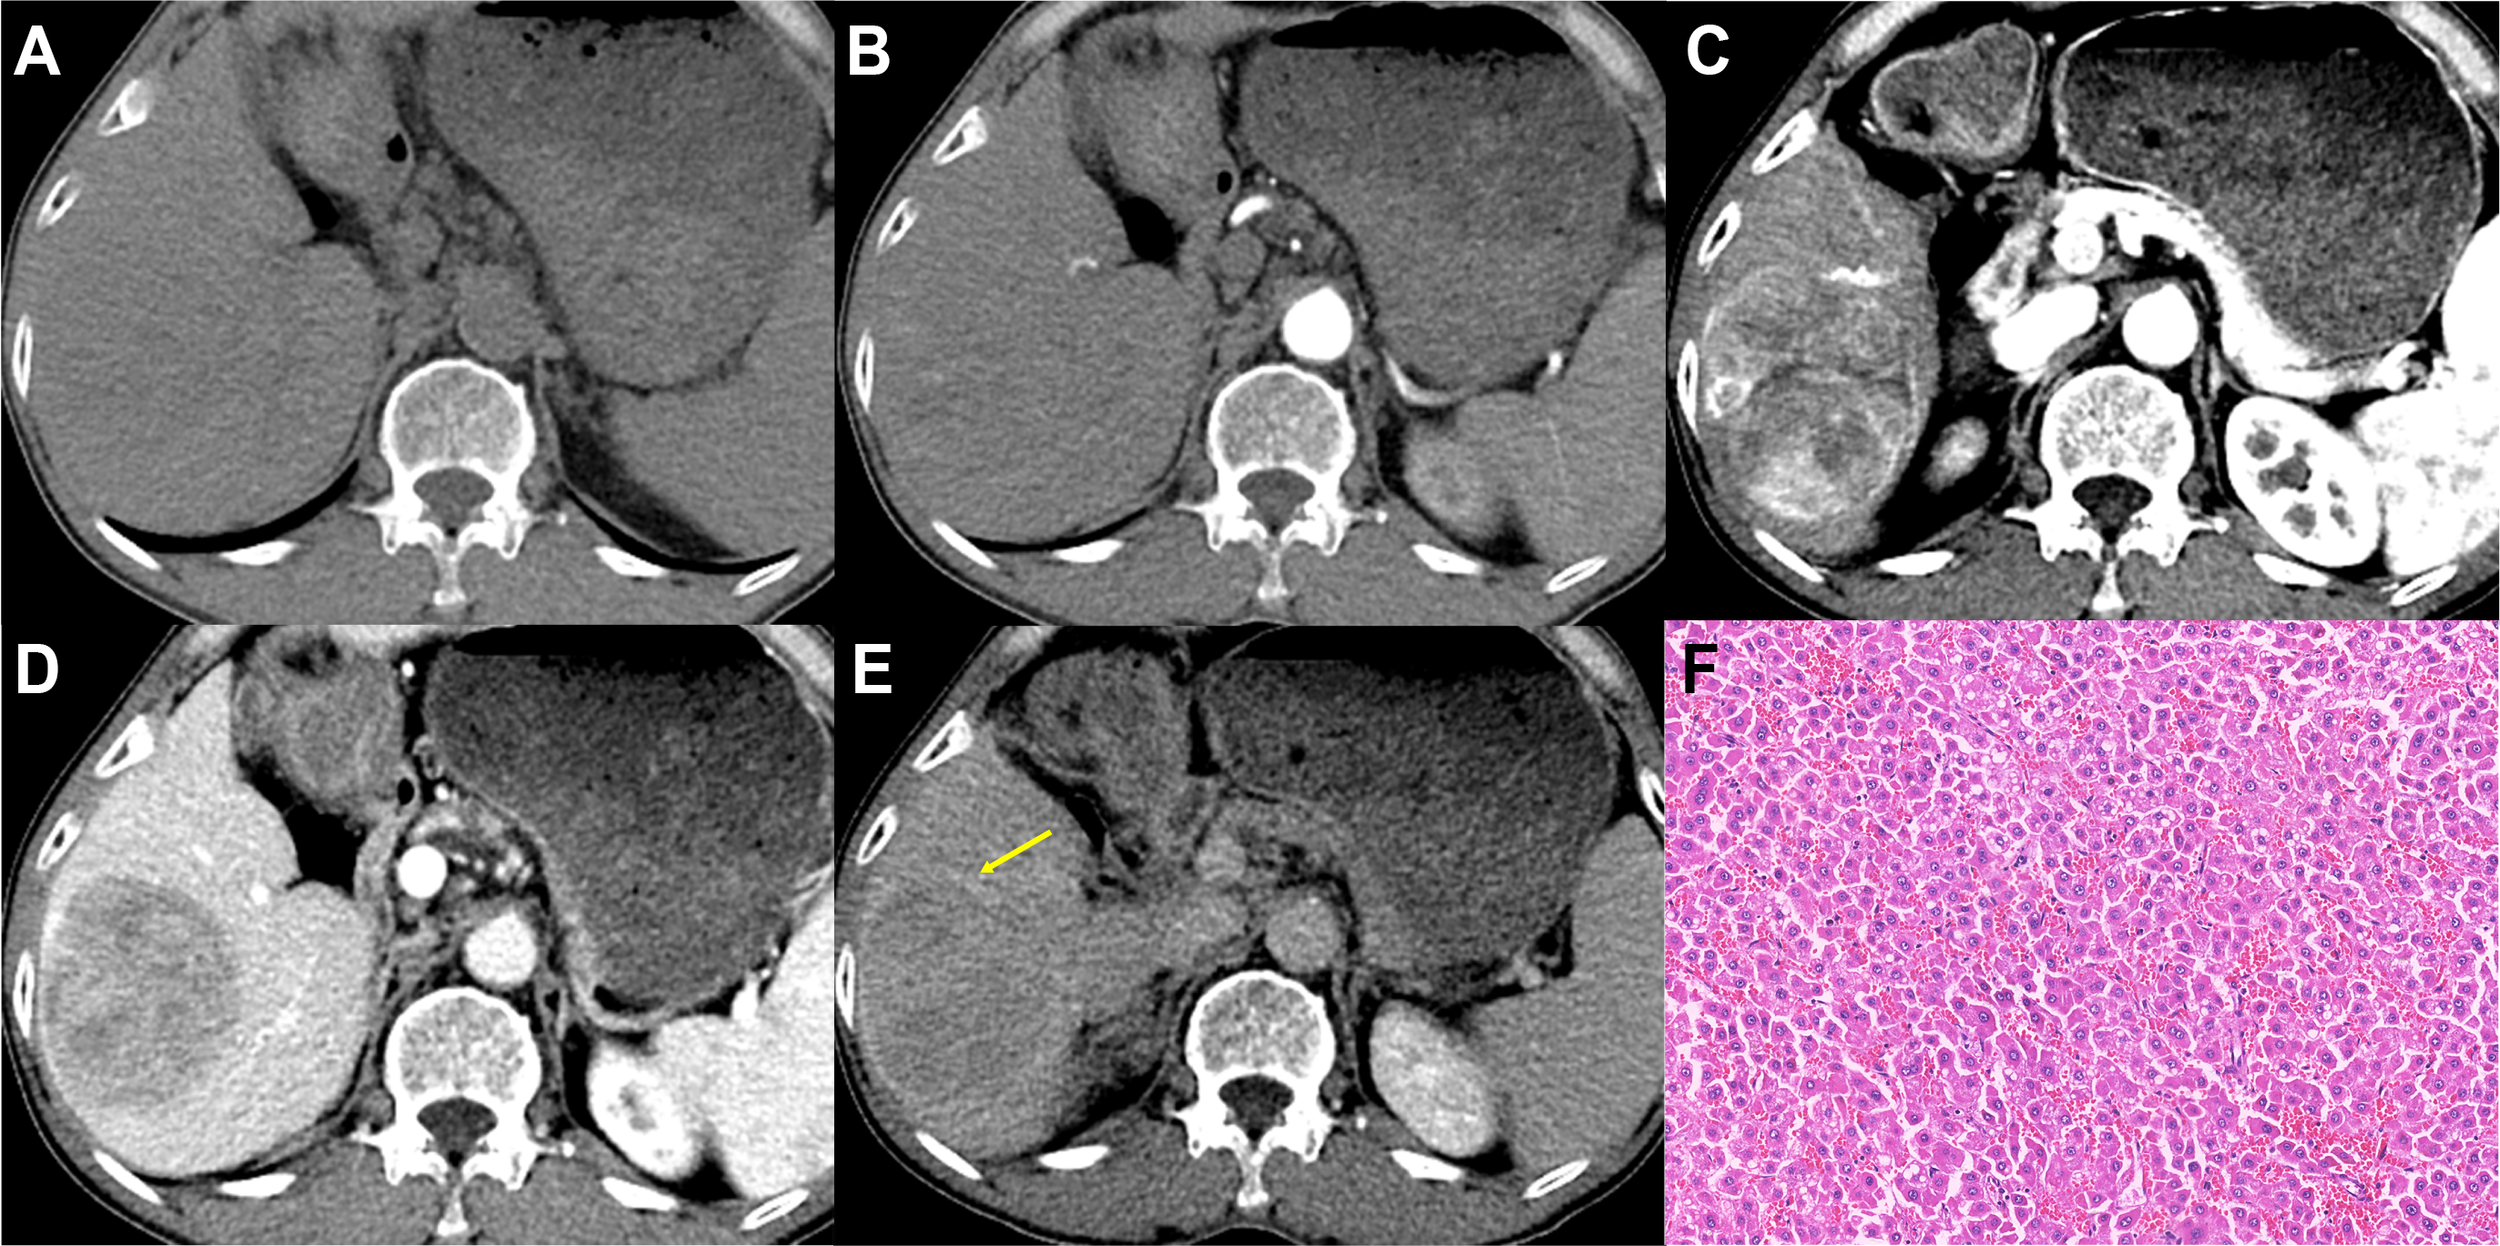

Figure 3

Imaging features and pathological information of a 62-year-old male non-MTM-HCC patient with an AFP level of 26.58 ng/mL and hemoglobin of 119 g/L. Multiphase axial contrast-enhanced CT (CECT) demonstrates iso-attenuation in the unenhanced phase (A) and early arterial phase (B). Strong and heterogeneous hyperenhancement (APHE) and little intratumor hypoenhancement are evident in the late arterial phase (C). Capsule enhancement (yellow arrow) and washout are demonstrated in the portal venous phase (D) and delay phase (E). Histopathology confirmed the diagnosis of non-MTM-HCC (F, original magnification, × 100; hematoxylin-eosin staining).